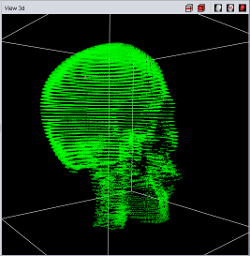

|

|

|

| Point Cloud | Marching Cube | Texture |

Currently four different segment visualization methods can be choosen.

The 3D segment visualization methods can be set for each individual segment. This can be done in the "view 3d" tool pane.